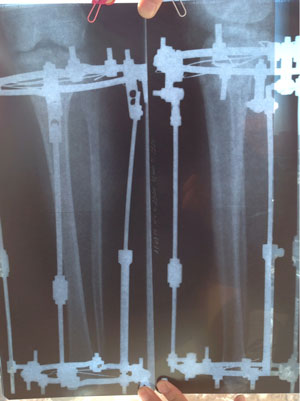

Ножки на фиксации, всё ок! Уезжаю домой на сращение!

Ножки на сегодня!

Здравствуйте Наташа и Николай Николаевич. Сегодня 40 дней со дня операции.все в порядке.